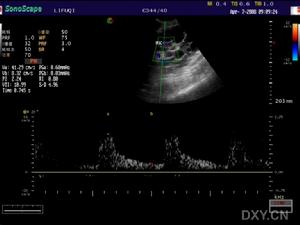

②功能上,舒張性心力衰竭患者的收縮功能一般良好,左心室射血分數(LVEF)大多正常,部分肥厚型心肌病患者LVEF超過70%。用M型超聲心動圖檢測二尖瓣前葉曲線的E峰、A峰峰值可用於判斷左心室舒張功能,E/A比值<1提示左心室舒張功能減退。都卜勒測定二尖瓣血流頻譜是評價舒張功能的簡單易行的常用方法,可揭示左心室舒張功能異常及其進展過程。舒張早期流速峰值(EPFV)、舒張晚期血流值(APFV)、舒張早晚期流速峰值比(EPFV/APFV)及舒張早期峰速減速度(DC)都是常用的指標。舒張性心力衰竭患者的EPFV、DC減低,APFV增高,EPFV/APFV小於1。此外,當左心室鬆弛性減退時,等容舒張時間(IVRT)延長;當左心室僵硬度增加時,IVRT縮短;當左心室鬆弛性和僵硬度均有異常時,二尖瓣血流頻譜可“偽正常化”。高齡、心率加快(大於90次/min)、左心室前負荷減小或後負荷增加時可出現假陽性。房室平面位移(atrioventricularplanedisplacement,AVPD)的測定最初用於評價收縮功能,方法是用M型超聲在心尖四腔觀中室間隔與二尖瓣前葉交界點、左心室側壁與二尖瓣後葉交界點位處和在心尖二腔觀中左心室前、後壁與二尖瓣葉的交界處等四個部位記錄收縮期房室平面的最大位移程度。1992年Alam等用AVPD法評價左心室舒張功能,發現左心室舒張功能異常患者時常表現為心房收縮所致的AVPD值在總的AVPD值中所占的比例增高,且這種改變與用脈衝都卜勒測量二尖瓣血流頻譜所得的A/E比值改變有良好相關。

肺靜脈血流頻譜分析也有助於評價左心室舒張功能。多數正常人肺靜脈血流頻譜為三相峰,由收縮峰(S)、舒張峰(D)及心房收縮峰(A)組成。正常時S低於D,但測值接近(參考值為0.55m/s);A很小,約為0.18m/s。左心室舒張功能異常的患者表現為右上肺靜脈血流頻譜S值升高、D值降低、S/D比值增加、A值升高,這種異常與左心室結構和功能密切相關。聲學定量(AQ)方法通過自動檢測心內膜邊界得出左心室面積隨時間變化的曲線及面積變化率(dA/dt)隨時間變化的曲線。後者為雙峰形態,即舒張早期峰值充盈率與舒張晚期充盈率。脈衝都卜勒超聲測量二尖瓣血流頻譜可以發現,E/A比值下降,而AQ方法可發現峰值充盈率/晚期充盈率比值下降。在有些無左心室肥厚的輕度高血壓患者,脈衝都卜勒超聲左心室充盈參數在正常範圍,而AQ方法可檢出E峰加速時間(AT)延長及早期充盈時間延長。脈衝都卜勒心肌顯像(DMI)技術通過在不同心肌節段放置取樣容積以進行在機定量分析,可檢出不同心肌節段受損的範圍和程度。舒張功能不全累及的心肌節段越多,左心室整體舒張功能的損害越大。另外,可用負荷試驗來提高早期舒張功能異常患者的檢出率,例如握力超聲心動圖試驗可用於高血壓患者潛在性舒張功能異常和心肌缺血的診斷。超聲心動圖對左心室舒張功能的檢測結果受許多因素如取樣容積的部位、聲速與血流方向的夾角、年齡、生化和代謝因素(血漿腦利鈉肽、血漿心房利鈉肽等)、藥物如血管緊張素轉換酶(ACE)抑制藥等的影響,故必須結合臨床、心臟形態及功能等資料進行綜合分析。